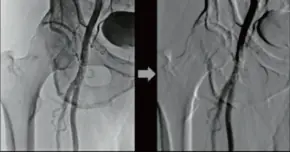

DSA

Dinamik Subtraksiyon Teknolojisi, vasküler dinamikleri görselleştirerek tanı ve tedaviye destek sağlar.

Dinamik subtraksiyon teknolojisi, damar yapılarını net bir şekilde ortaya

çıkarır.

Akıllı zamanlama ve hassasiyet ile anjiyografiyi geliştirir.